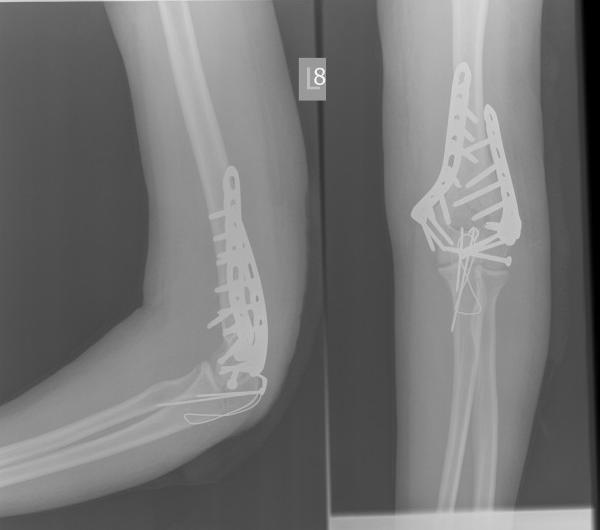

Ta kość, która jest prostopadła, powinna być równoległa, tak. W wyniku wielu dziwnych przygód z naszą ukochaną, polską służbą zdrowia, już tydzień później wyglądało to tak.

A kolejny tydzień później przyjęło wygląd mniej-więcej obowiązujący do teraz: